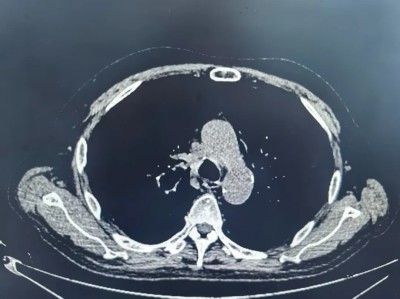

张大叔第三疗程治疗前后对比

治疗第一个疗程后

治疗第三个疗程后

3月下旬,顺利完成第3疗程治疗。复查结果令人振奋:肿瘤显著缩小,侵犯右主支气管的病灶大幅退缩,生活质量明显提升。